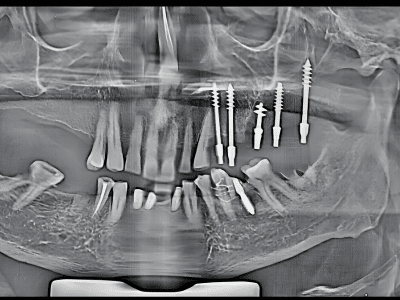

Periodontics, Dental Implants, and Advanced Gum Care. With a BDS and MDS in Periodontics, she

provides expert treatment for gum diseases, receding gums, and dental implant procedures using the

high standards of hygiene and comfort. Her expertise includes laser dentistry, cosmetic smile

From routine checkups to complex gum treatments, dental implants, laser dentistry, root canal treatments (RCT), and smile

We use advanced dental equipment, including laser dentistry, digital X-rays, and minimally invasive techniques, ensuring precision, safety

Dr. Bhardwaj specializes in Periodontics, offering treatments for gum diseases, dental implants, laser dentistry, root canal treatments (RCT), teeth whitening, smile makeovers, and general dental care.